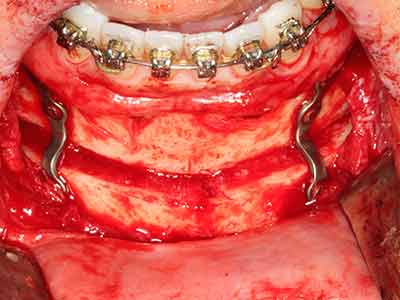

Когато се извършват хирургични процедури върху кост в непосредствена близост до чувствителни структури като кръвоносни съдове или нерви, ротиращите инструменти създават значителен риск за ятрогенно нараняване. Пиезоелектрическите апарати могат да бъдат от помощ при препарация на костно покритие и отстраняване на твърда кост близо до нерви, особено за оголване на нервите след ятрогенно нараняване, както и по време на латерализация на нервите за резекционни и реконструктивни процедури или поставяне на имплант (Фиг. 17-20). Лекият контакт между пиезонакрайника и нерва по принцип не води до нараняване, но ако действате непредпазливо с трионообразни движения или приставки за остатъчен костен субстрат, може да причините временно или перманентно увреждане на нерва. Въпреки това, рискът от увреждане се счита за много по-малък, отколкото при употреба на триони или ротиращи инструменти (Pereira, Gealh et al. 2014).